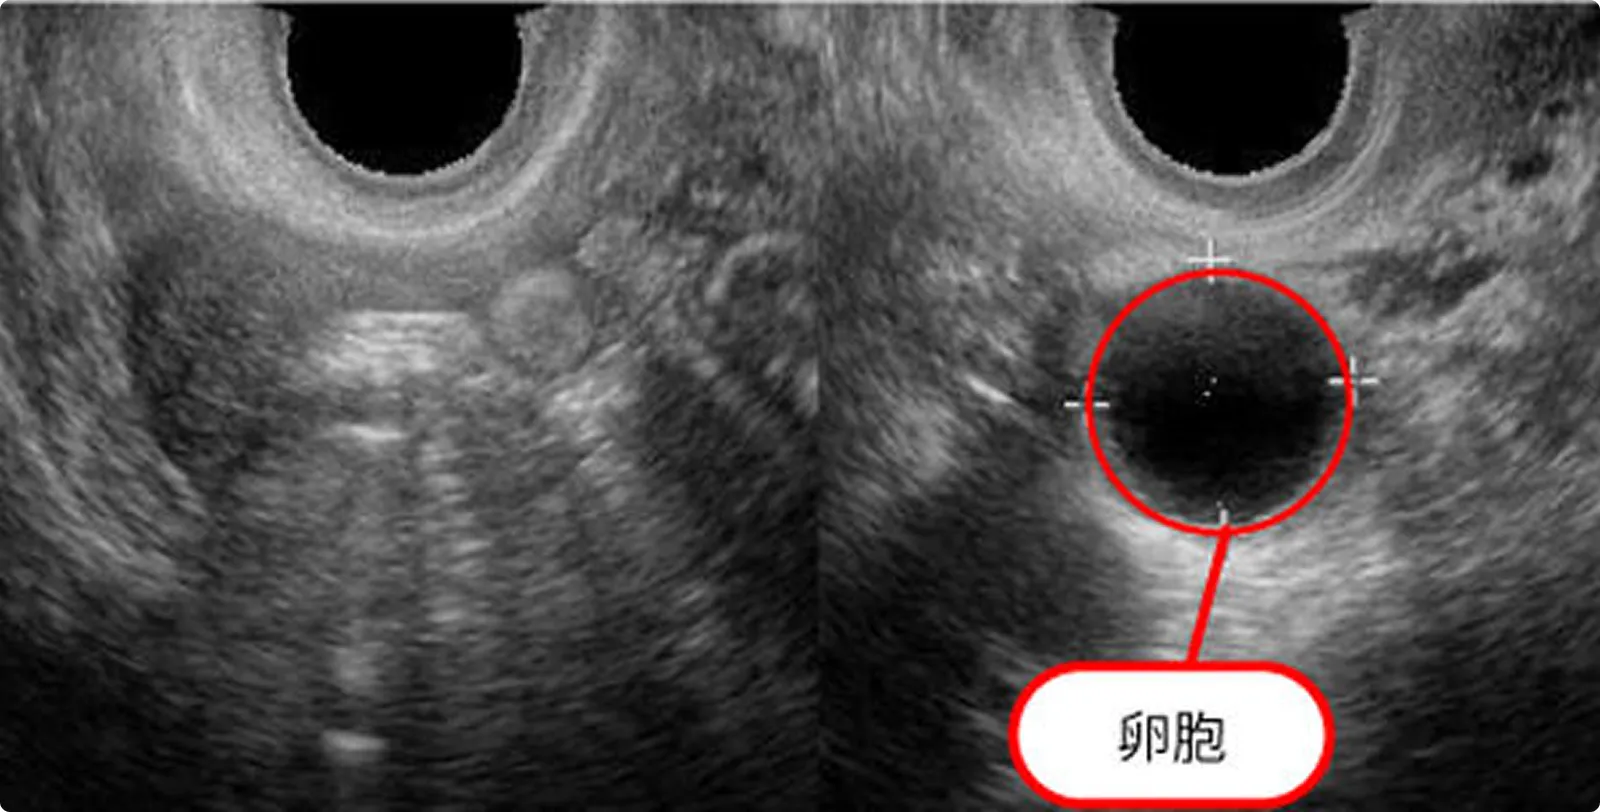

排卵直前の主席卵胞

通常約20mmに卵胞が達した頃に排卵します。